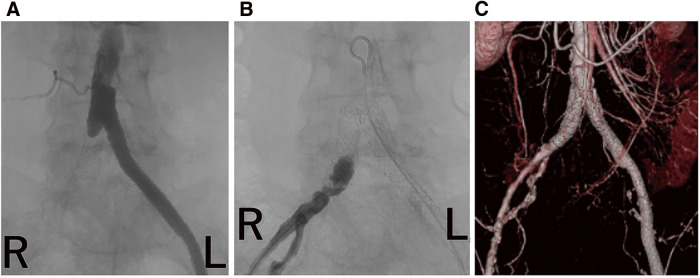

The patient previously underwent surgery for cervical cancer. She reported intermittent claudication, and computed tomography (CT) revealed total occlusion of the left iliac artery. We conducted endovascular treatment (EVT) using balloon-expandable covered stents (BECS). The patient underwent colostomy closure after EVT. The patient reported intermittent claudication beginning the day after the procedure. The CT showed a collapse of the distal side of the stent implanted in the right common iliac artery, accompanied by localized thrombo-occlusion. During open surgery, metal hooks typically affect the iliac artery; force transmission through the tissue may indirectly compress the iliac artery, leading to BECS failure.

患者曾接受过宫颈癌手术。她报告出现间歇性跛行,计算机断层扫描(CT)显示左侧髂动脉完全闭塞。我们使用球囊扩张覆盖支架(BECS)进行了血管内治疗(EVT)。EVT 后,患者接受了结肠造口术。术后第二天,患者出现间歇性跛行。CT 显示,植入右侧髂总动脉的支架远端塌陷,并伴有局部血栓闭塞。在开放手术中,金属钩通常会影响髂动脉;通过组织传递的力可能会间接压迫髂动脉,导致 BECS 失灵。